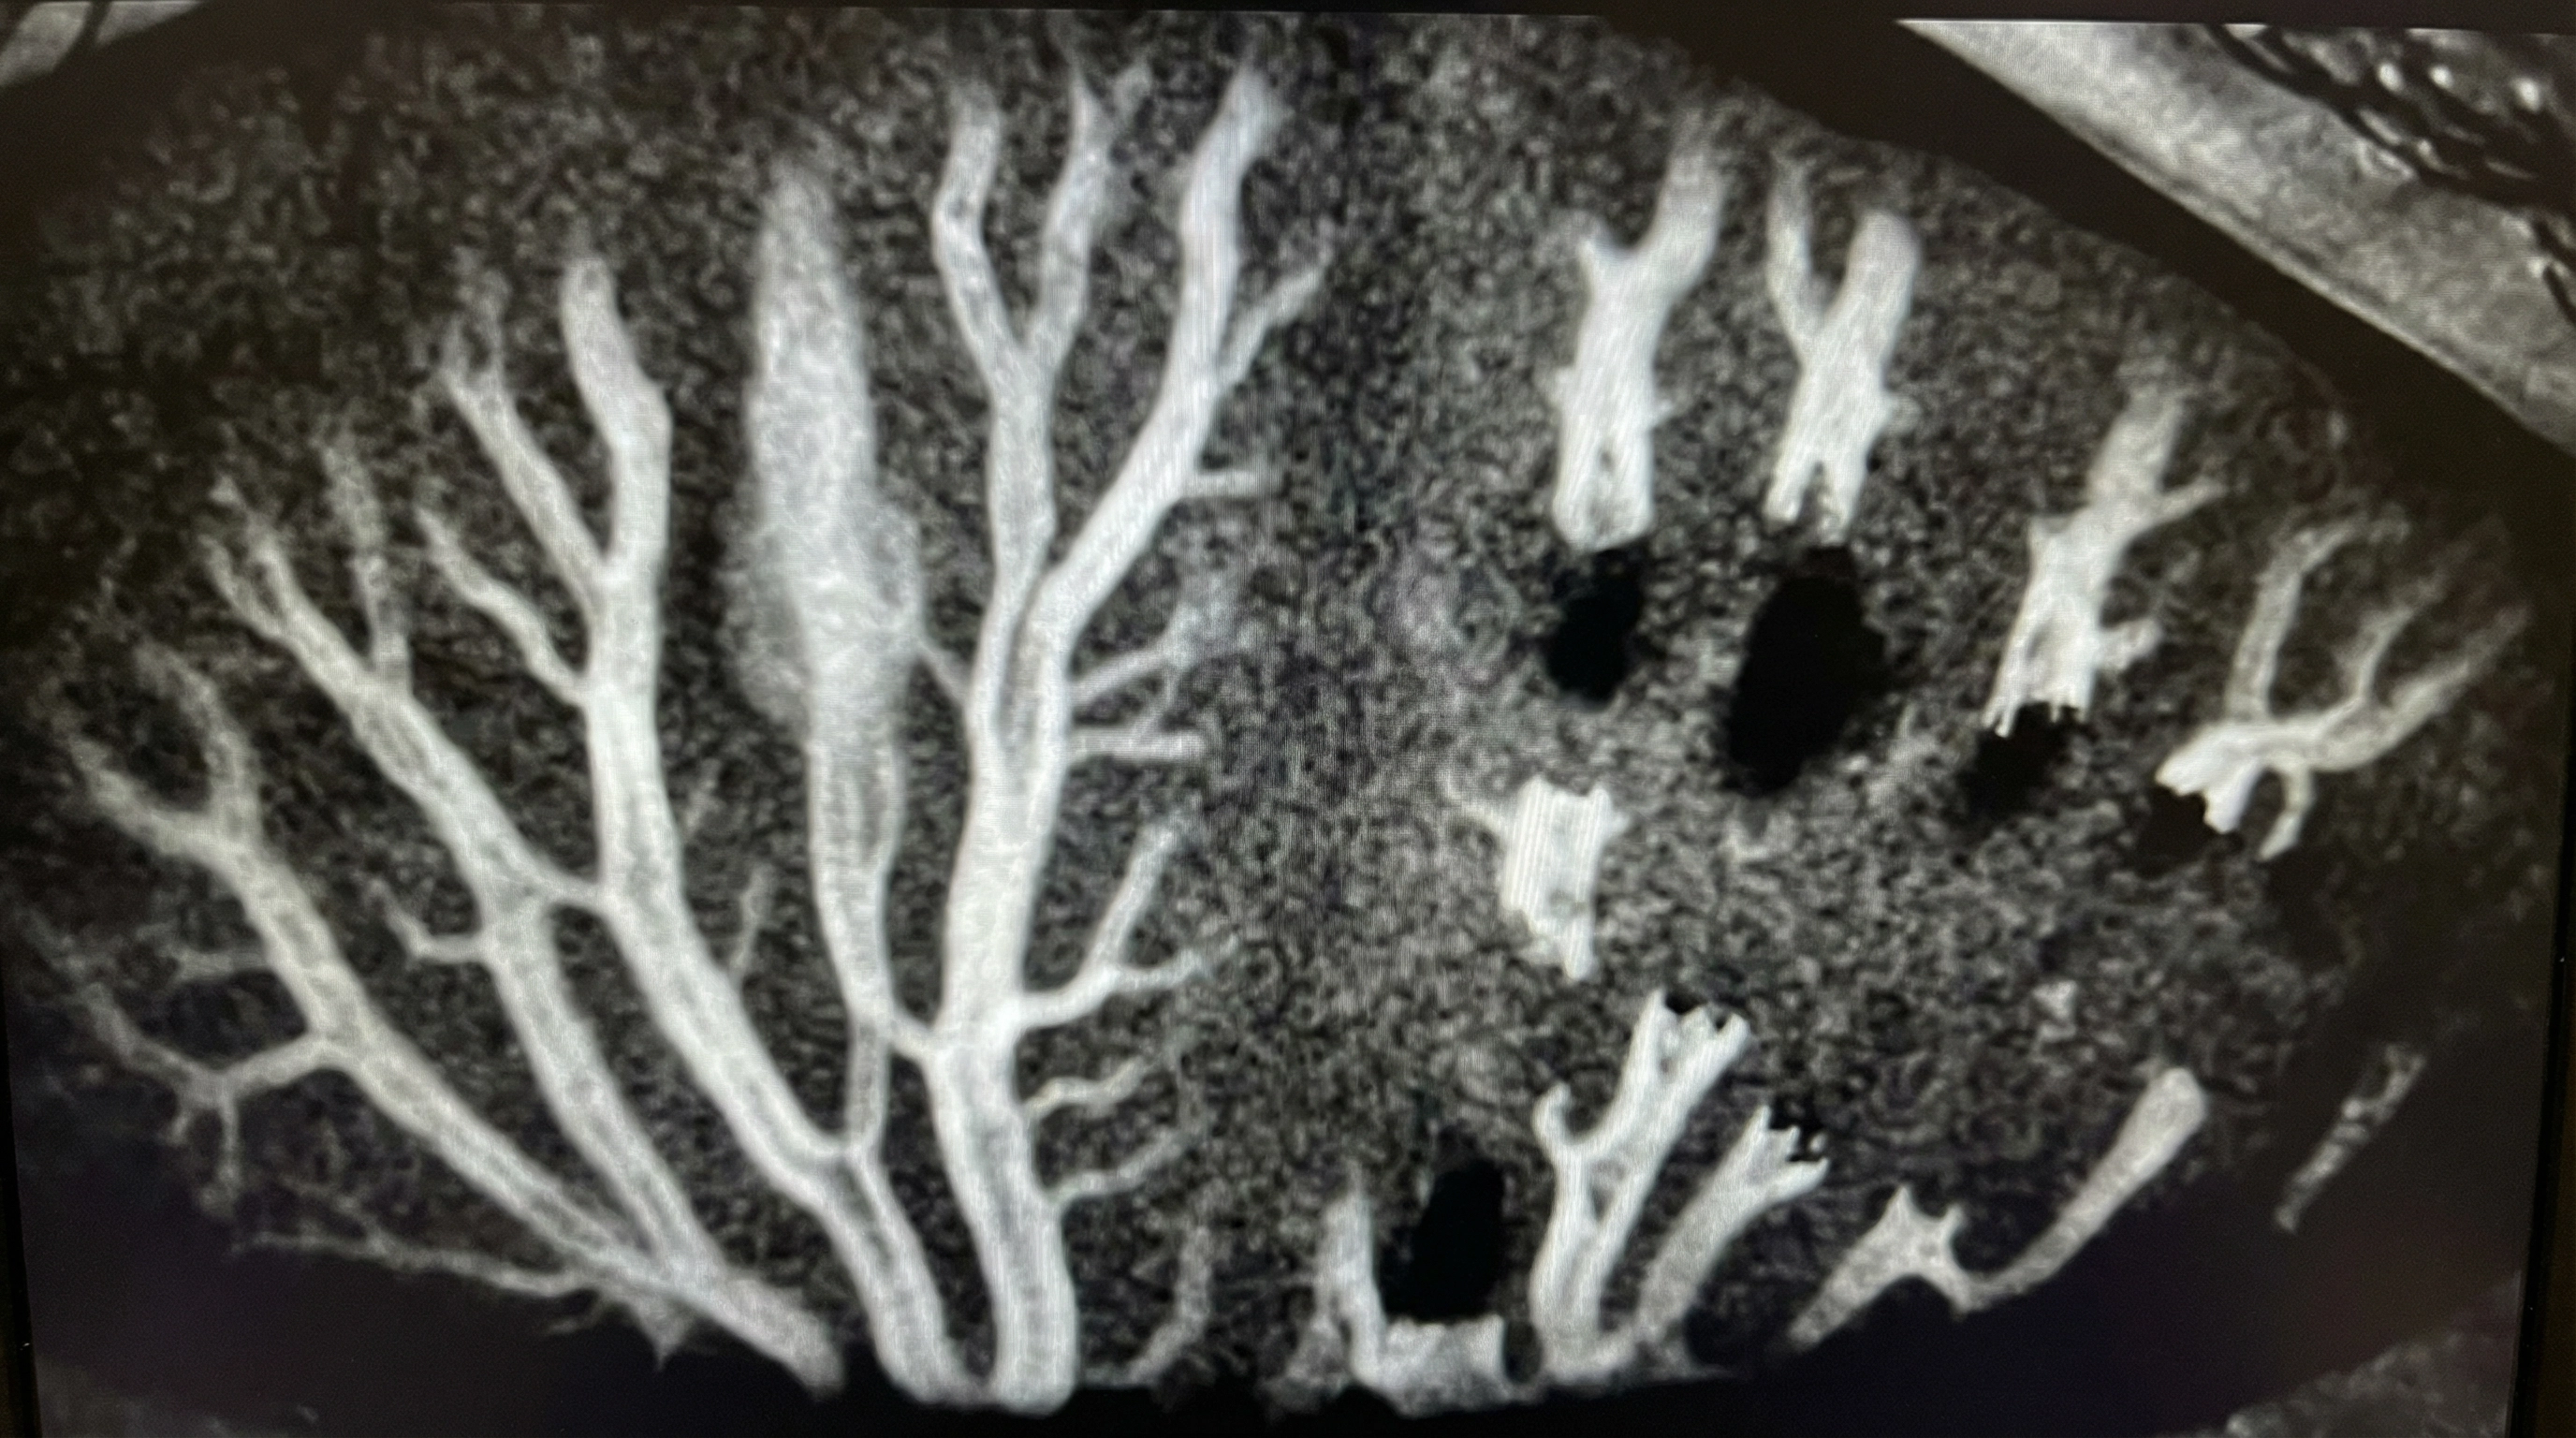

Meibomian Gland Imaging

High-resolution imaging shows the structure of your oil glands so we can see blockages before they cause permanent damage.